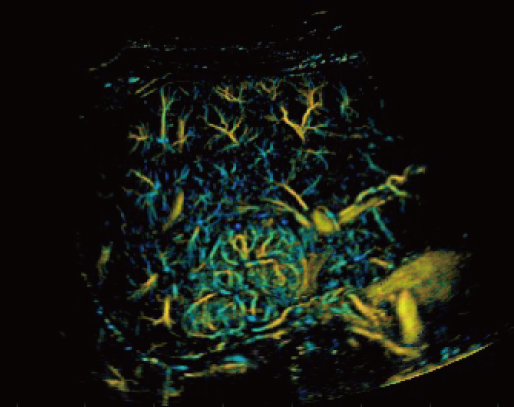

Aangestuurd door het AIT platform levert de Resona A20 een alles-in-├®├®n, ge?ntegreerde oplossing voor beeldvorming met superresolutie, iets wat voorheen moeilijk haalbaar was. SR CEUS onthult de ingewikkelde microcirculatiedetails van laesies op micronniveau, wat helpt bij onderzoeken naar microcirculatoire perfusie in oncologie.

Mogelijkheden voor microvasculaire detectie

Focale nodulaire hyperplasie | Richtingskaart